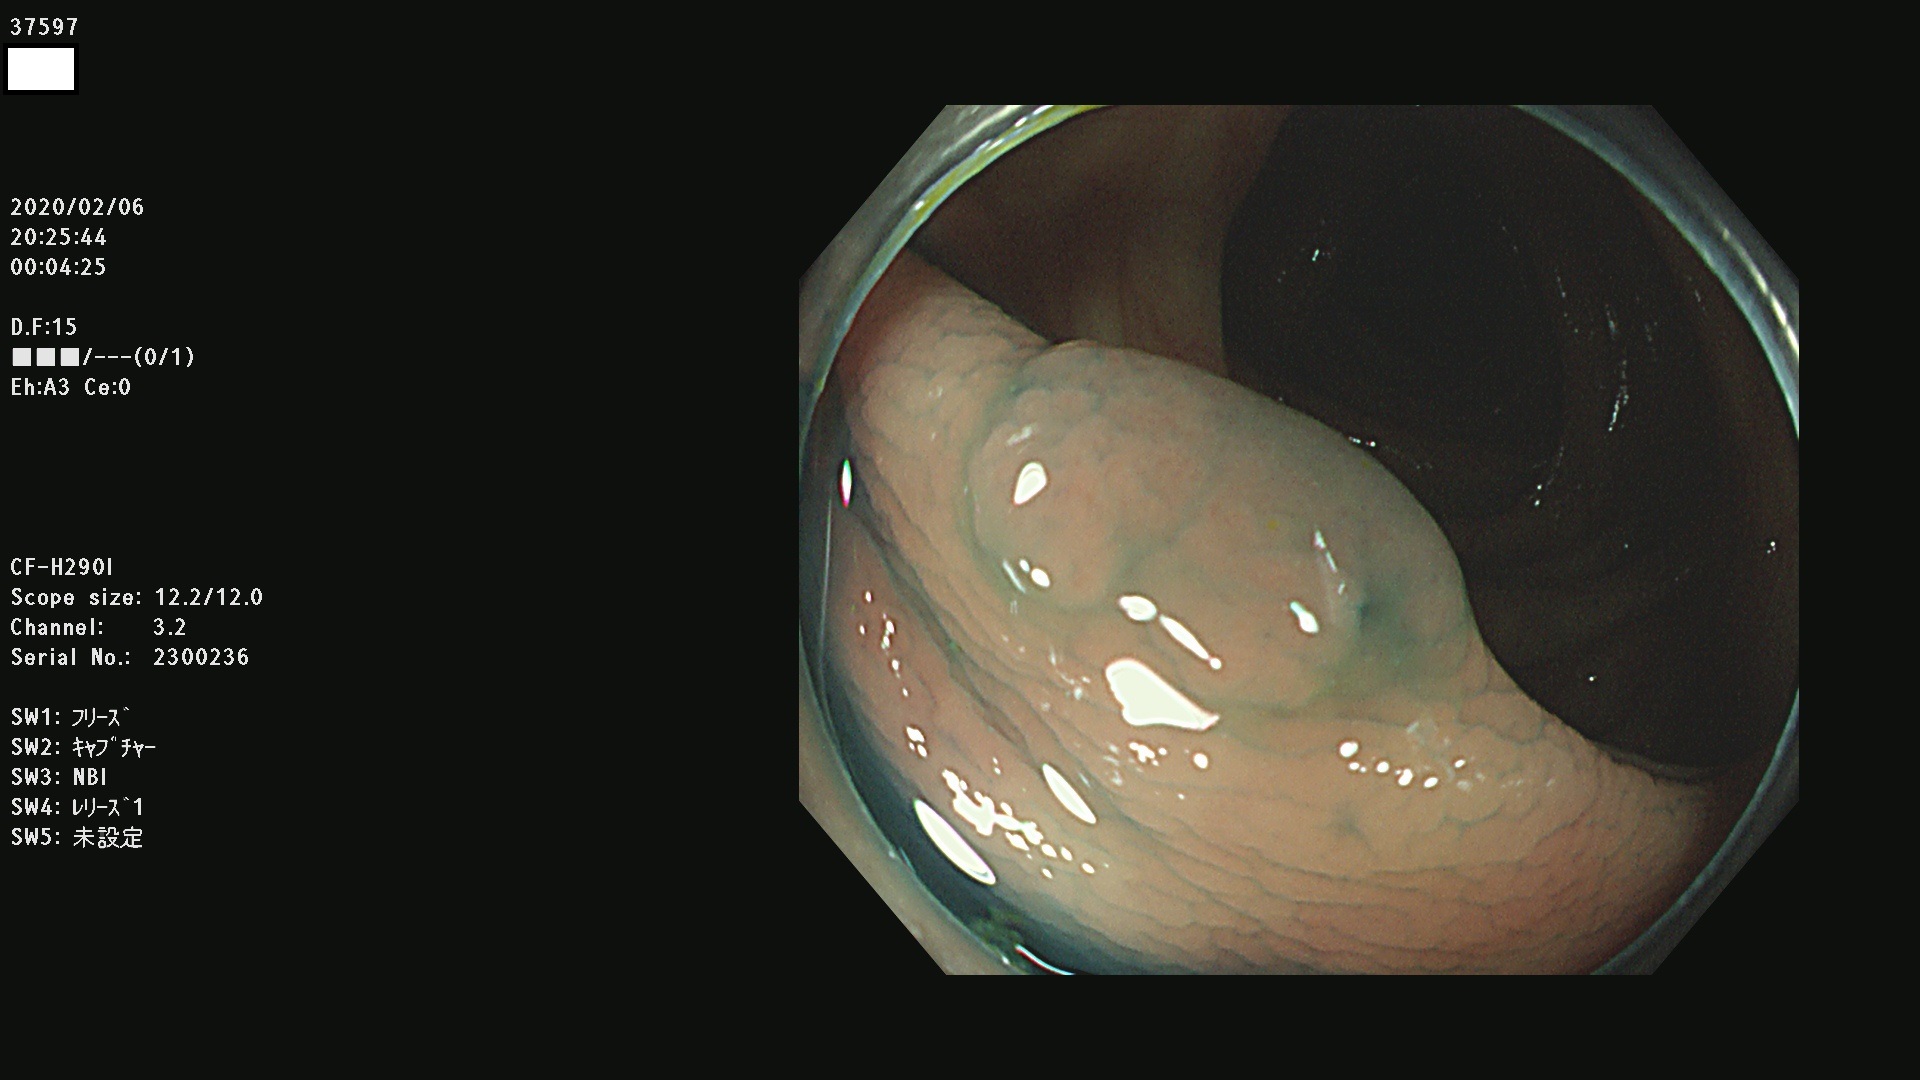

腺腫発見率 67 % (カルテ番号 37500〜37599の100名の方の検査結果で集計)大腸癌検診最新情報

以下のカルテ番号の方に腺腫(Adenoma,Group3〜5)が見つかりました(集計法)

37500 37502 37503 37505 37508 37509 37510 37511 37512 37513 37514 37517 37519 37520 37521 37525 37526(SSAPのみ) 37527 37528 37529 37531 37532 37533 37534 37536 37538(SSAPのみ) 37539 37541 37542 37543 37547 37548 37549(SSAPのみ) 37550 37552 37555 37556 37561 37562 37563(SSAPのみ) 37564 37565 37566 37567 37568 37570 37571 37572 37573 37574 37575(SSAPのみ) 37576 37577 37579 37580 37582 37583 37586(SSAPのみ) 37587 37588(SSAPのみ) 37590 37593(SSAPのみ) 37594 37596 37597(SSAPのみ) 37598 37599

発見困難で危険性の高い平坦型病変(上記100名より抽出) ![]()